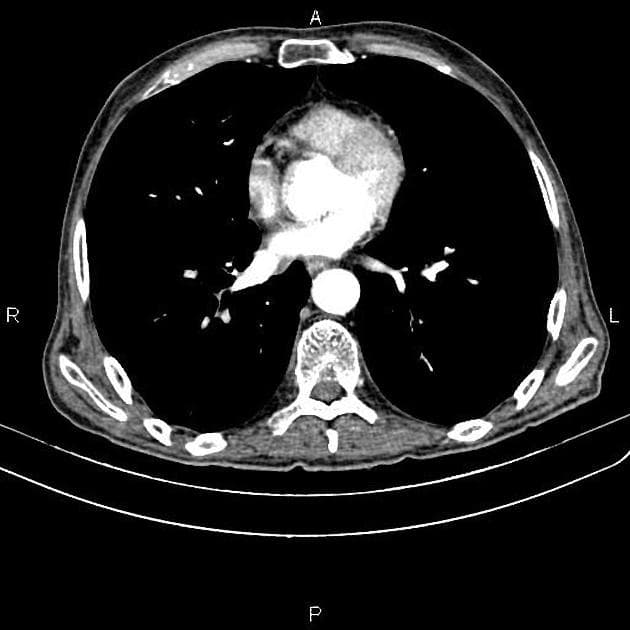

Chẩn đoán & Phát hiện

Thành dạ dày dày không đối xứng và tăng quang mạnh do thâm nhiễm u tại tâm vị và phần gần bờ cong nhỏ, kèm theo nhiều hạch bạch huyết lớn quanh dạ dày. Các hạch bạch huyết lớn này tiếp xúc sát với thùy gan trái và tuyến thượng thận trái, cùng với tình trạng tuyến thượng thận trái lớn nhẹ, gợi ý có sự xâm lấn tại chỗ. Có một hạch bạch huyết lớn nằm ở chuỗi hạch dưới hoành phải. Ngoài ra, có một khối lớn, không đồng nhất với bờ không đều ở gan, biểu hiện tăng quang ngoại vi sớm kèm washout muộn và hoại tử trung tâm rộng. Có tình trạng giãn nhẹ ống mật trong gan ở vùng ngoại vi của khối u. Phần còn lại của gan bình thường và không có dấu hiệu của xơ gan nền. Có một nang kích thước 8 mm ở lách. Một vài nang nhỏ cạnh bể thận được ghi nhận ở cả hai thận, quan sát rõ hơn trên các hình ảnh thì bài tiết. Bệnh nhân đã được thực hiện sinh thiết khối u dạ dày qua nội soi và sinh thiết kim lõi khối u gan dưới hướng dẫn siêu âm. Kết quả giải phẫu bệnh và hóa mô miễn dịch xác nhận ung thư biểu mô tuyến dạng tế bào gan nguyên phát của dạ dày kèm di căn gan. THẢO LUẬN: Trường hợp này minh họa một ca ung thư biểu mô tuyến dạng tế bào gan tiến triển ác tính của dạ dày, xuất phát từ tâm vị và phần gần bờ cong nhỏ ở một bệnh nhân lớn tuổi, biểu hiện với di căn hạch vùng tiến triển và di căn gan lớn, nồng độ AFP huyết thanh cao, cùng các đặc điểm hình ảnh có thể rất giống với ung thư biểu mô tế bào gan nguyên phát. Ung thư biểu mô tuyến dạng tế bào gan của dạ dày là một loại ung thư dạ dày hiếm gặp, có độ ác tính cao, về mặt mô học giống với ung thư biểu mô tế bào gan và thường sản sinh alpha-fetoprotein (AFP). Nó chiếm khoảng 1% các trường hợp ung thư dạ dày và thường được phát hiện ở giai đoạn muộn với di căn gan và di căn hạch. Ung thư biểu mô tế bào gan nguyên phát và ung thư biểu mô tuyến dạng tế bào gan của dạ dày di căn gan có thể có hình thái rất giống nhau; tuy nhiên, chúng khác nhau về bối cảnh lâm sàng, đặc điểm hình thái và hóa mô miễn dịch.

- "Hình ảnh di căn gan có thể giống HCC nguyên phát với tăng quang sớm và washout muộn."